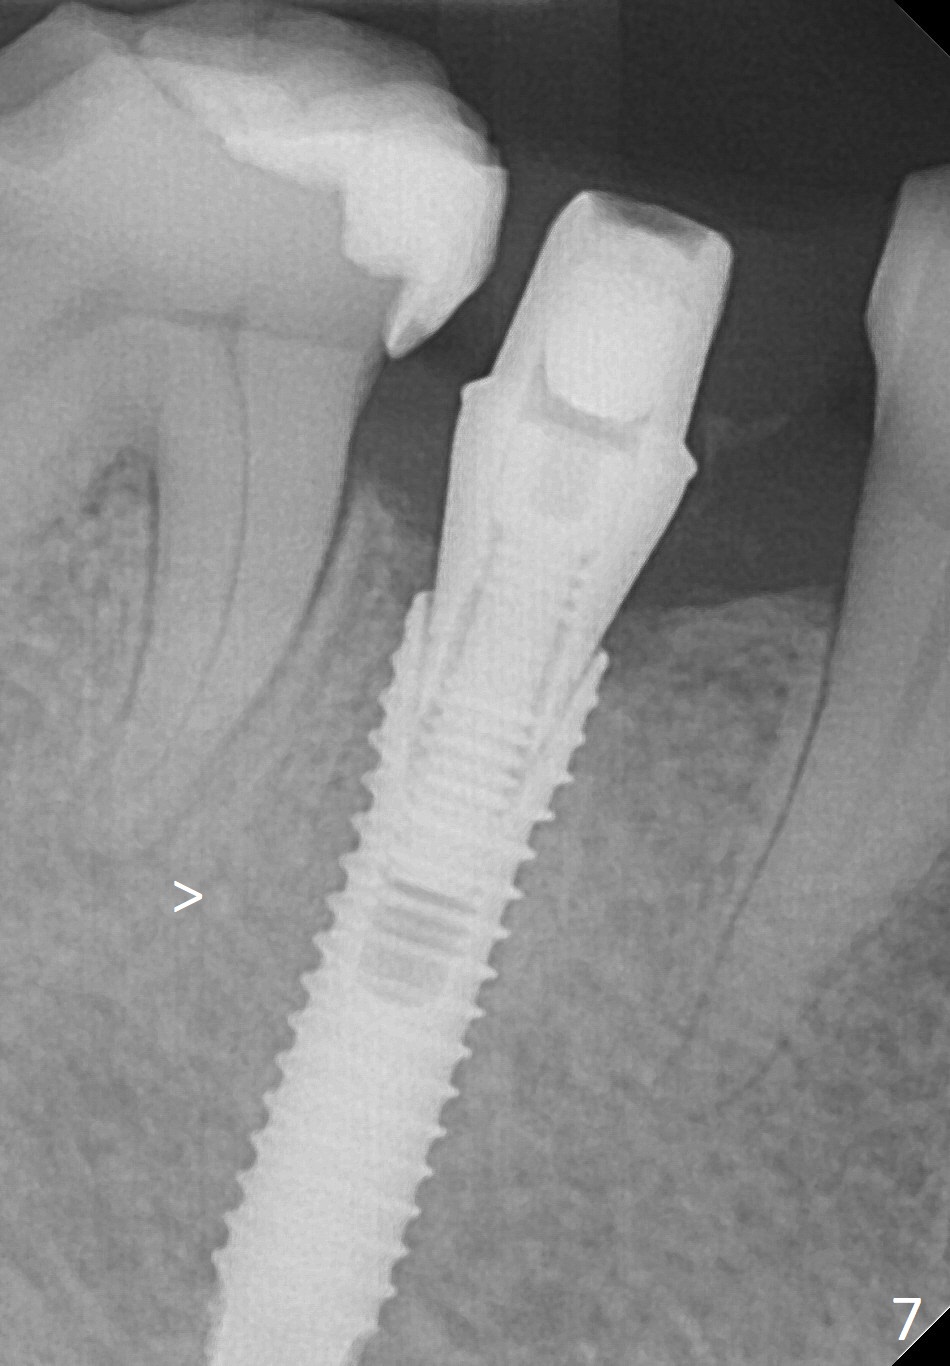

To reduce the chance to injury the buccally located loop, the osteotomy should be as lingual as possible. Initial depth is 19 mm (gingival level, Fig.3). In fact all of the three intraop PAs (Fig.3-5) do not show the Mental Loop until panoramic X-ray is taken immediately postop (Fig.6). There is no postop paresthesia. There appears no gap around the implant 3.5 months postop (Fig.7 >).

A 67-year-old woman fractures the tooth #29 three months post RCT. There is persistent periapical radio-lucency (Fig.1 yellow dashed line), which is close to the Mental Loop (red dashed line). Since the root of the affected tooth deviates distal, osteotomy will be established mesial (Fig.2). In fact it is not so easily accomplished; the osteotomy is initiated as mesial as possible (Fig.3 (yellow dashed line: original socket)). When a 3.8x16 mm implant is being placed, it is distal (Fig.4). The MO composite of the tooth #30 has to be trimmed for fabrication of an immediate provisional (Fig.5 <).